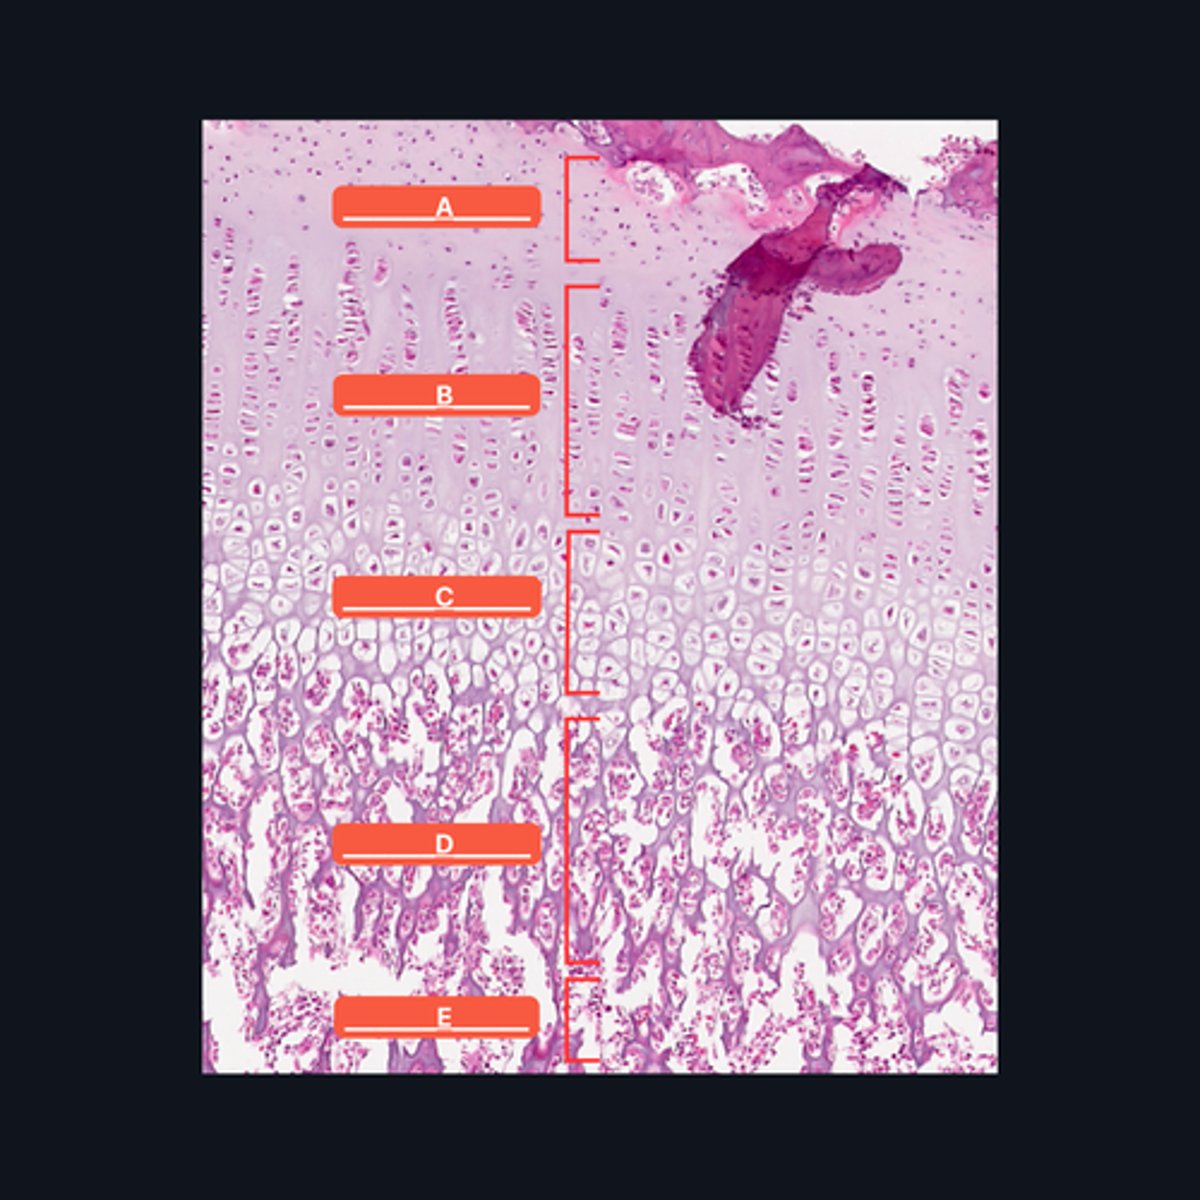

A - Zone of Resting Cartilage Cells

B - Zone of Proliferation

C - Zone of Maturation

D - Zone of Calcification

E - Zone of Ossification

Identify the pointed structures

B - Zone of Proliferation

Which pointed structure is the zone where instestitial growth occurs and what zone is it?

E - Zone of Ossification

Which pointed structure and what zone where many of the cavities left by cartilage cells merge to form marrow cavities?

C - Zone of Maturation

Which pointed structure and what zone do not divide anymore?

A - Zone of Resting Cartilage Cells

Which pointed structure and what zone anchors the epiphyseal plate to the epiphysis?

D - Zone of Calcification

Which pointed structure and what zone where the cartilage matrix is calcified